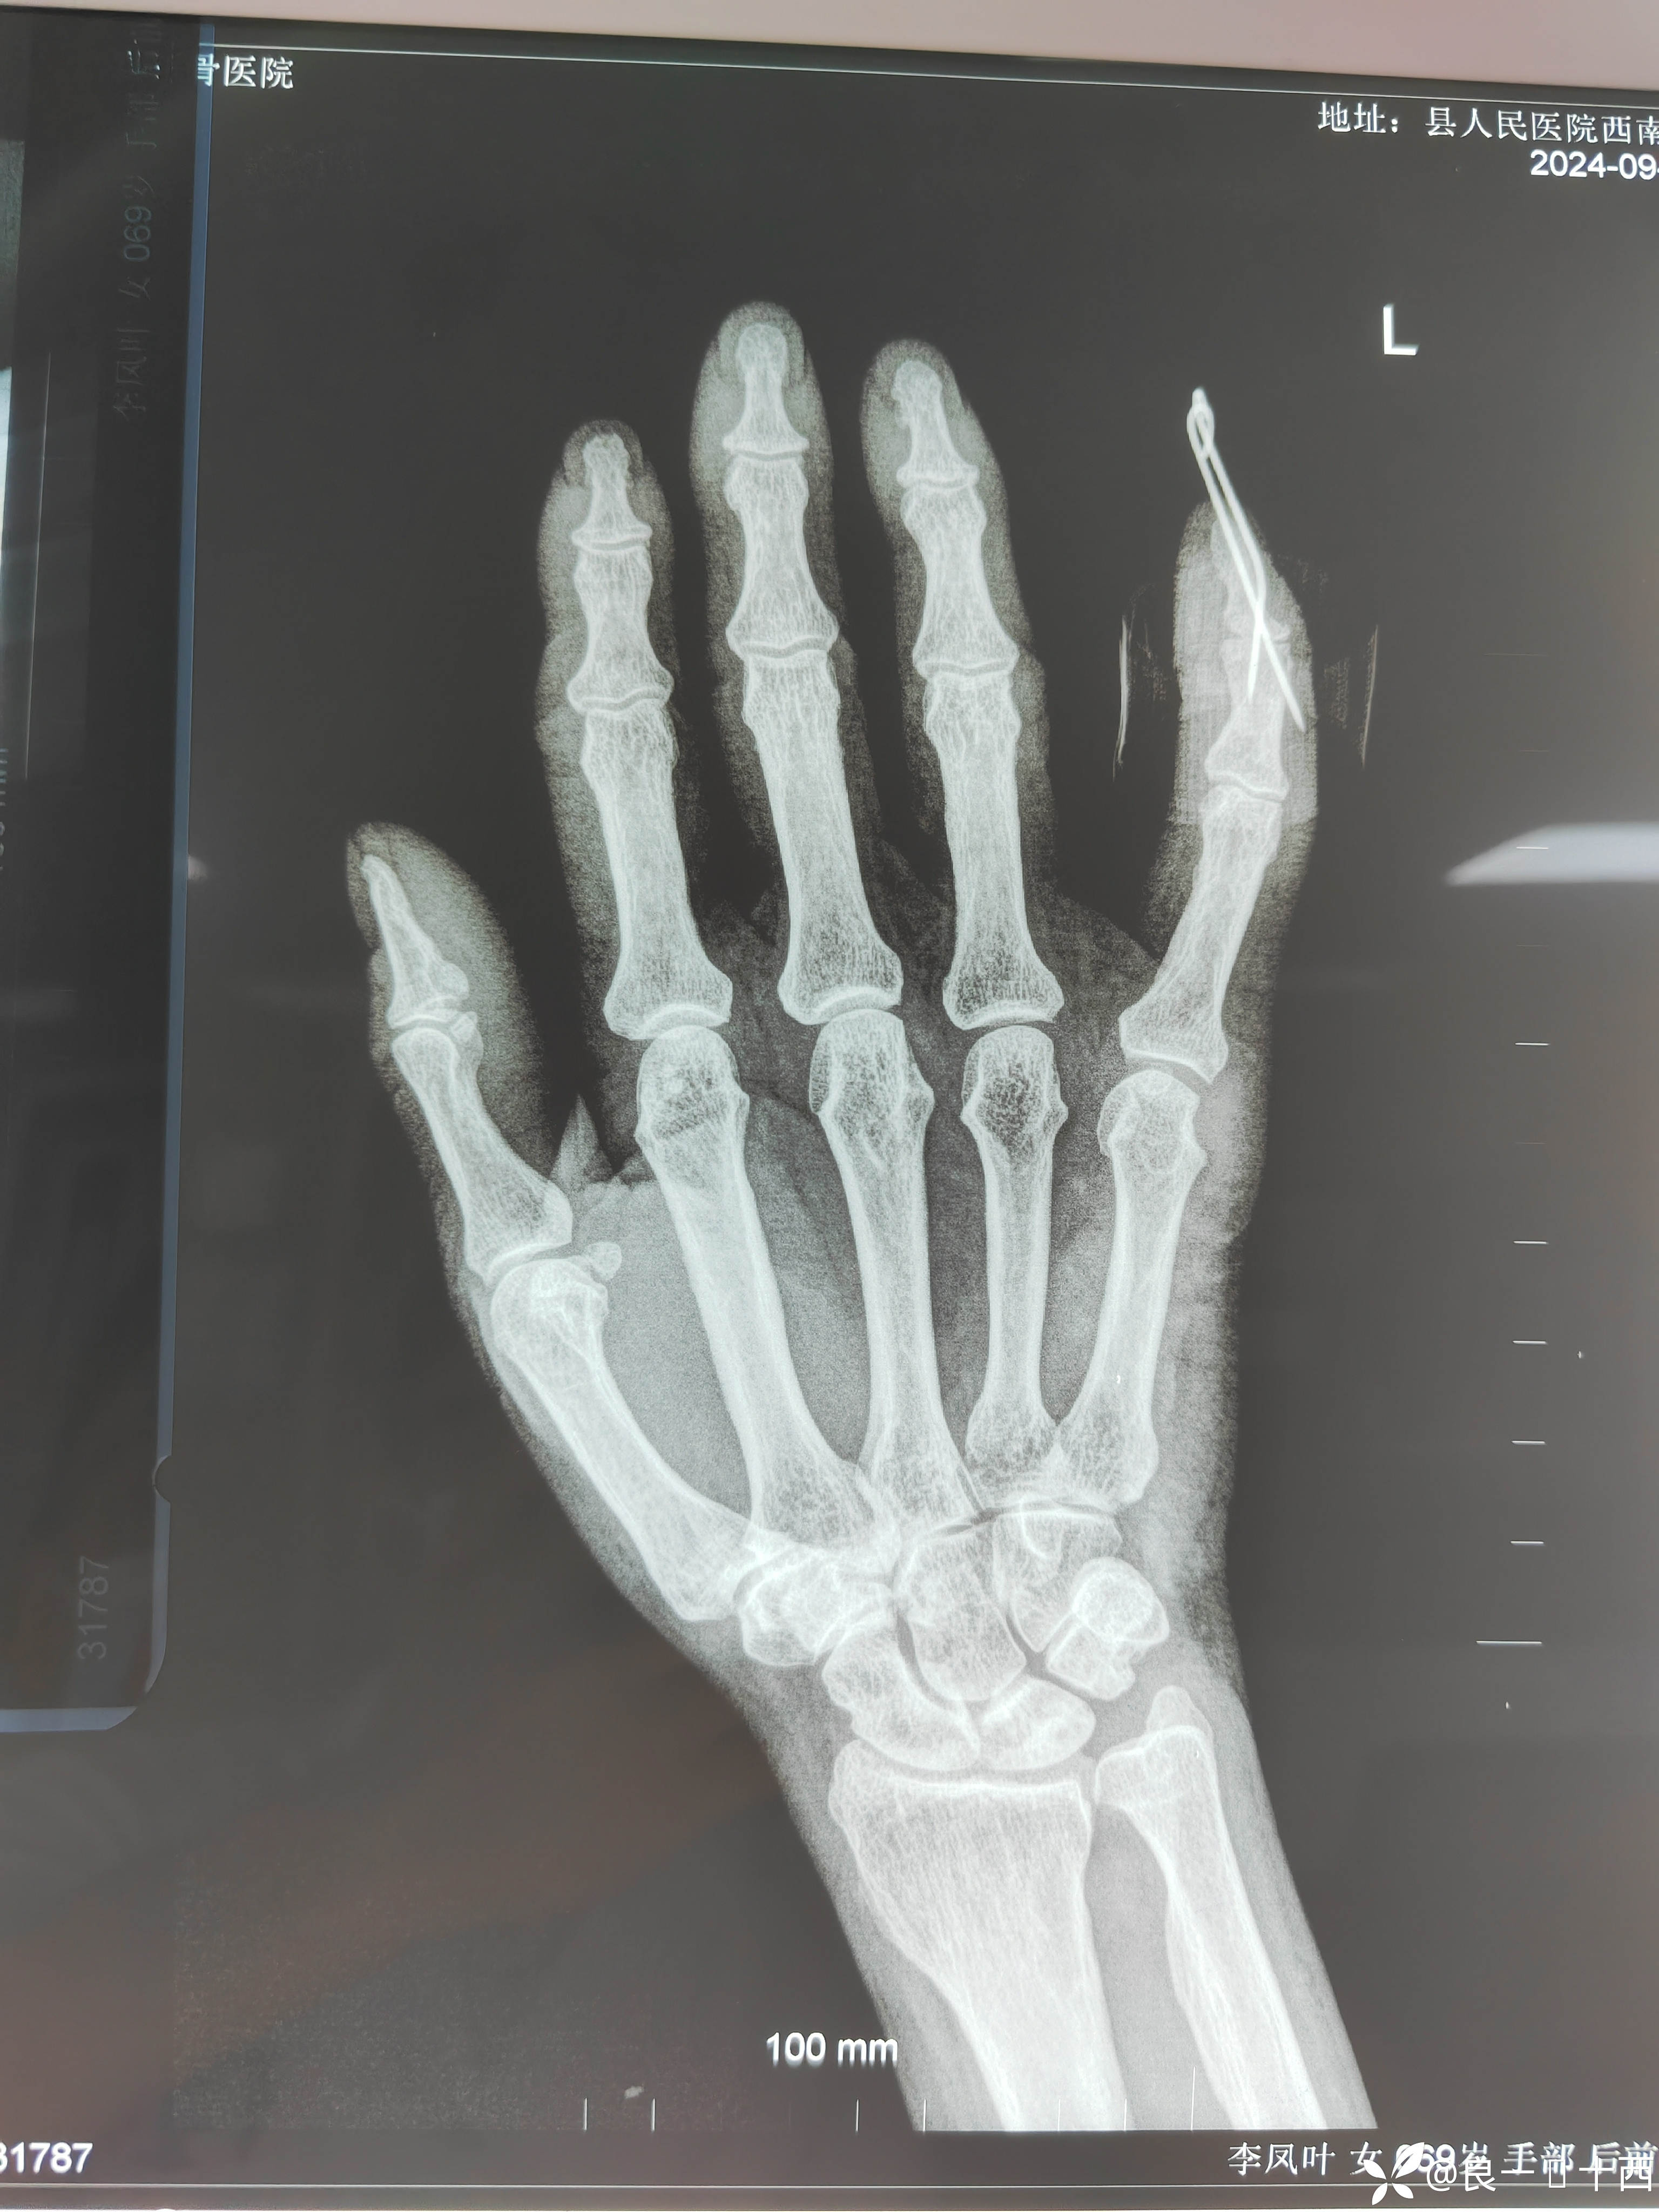

【患者信息】:李XX,女,69岁,

【检查】:外院DR片:左手小指末节基底部骨折。

【临床诊断】:左手小指伸肌腱止点开放性骨折